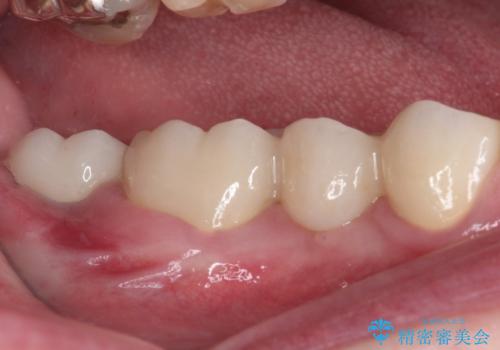

抜歯してからインプラント埋入までには時間がかかるため、その間に下顎左右臼歯の金属のブリッジをオールセラミックへ変えていくこととしました。

目立つ部分の銀歯や気になる変色歯をまとめてきれいに仕上げることができました。